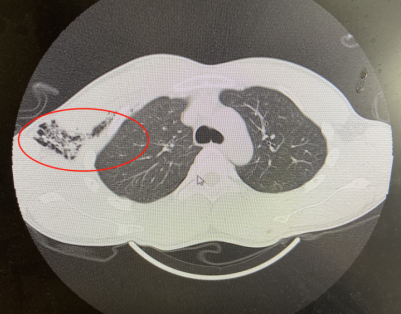

普外科的李素方主任接到急诊通知后,查看患者,考虑患者胸腹贯通伤、肛门开放性损伤、右肺贯通伤、右侧血气胸、直肠破裂等多处损伤。

肺部气体跑到皮下

肺部戳洞